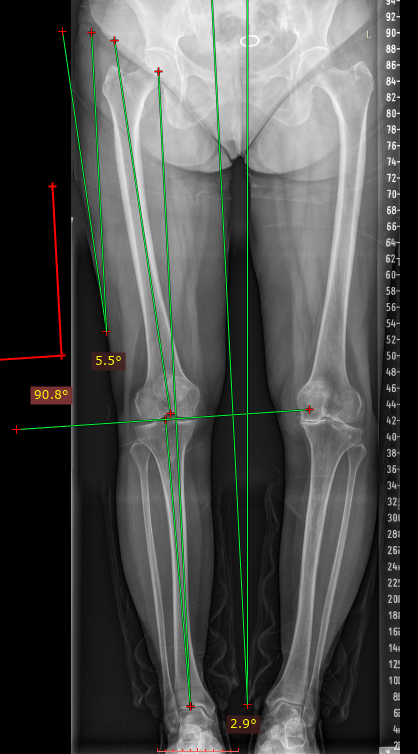

下肢力线测量(Lower extremity force line measurement)